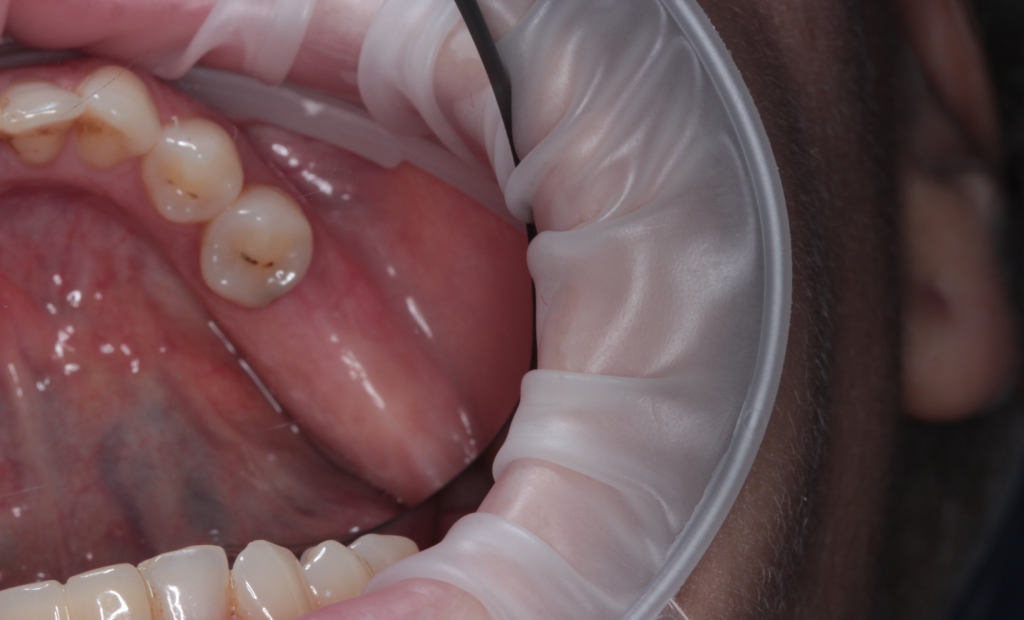

Описание клинического случая:

Клинический случай Узденовой Зульфы Альбертовны